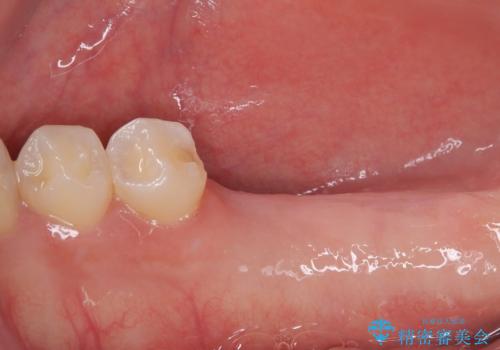

「1年前に抜歯した右下の奥歯にインプラントを入れたい」とのことで来院されました。

インプラント希望部位は右下第一大臼歯と第二大臼歯です。

しかし、噛み合わせの相手である右上の第二大臼歯が、長期間噛み合う歯がなかった影響で**挺出(歯が下に伸びてくる状態)してしまっており、このままではインプラントを埋入して被せもの(上部構造)を入れるためのスペースが不足している状態でした。